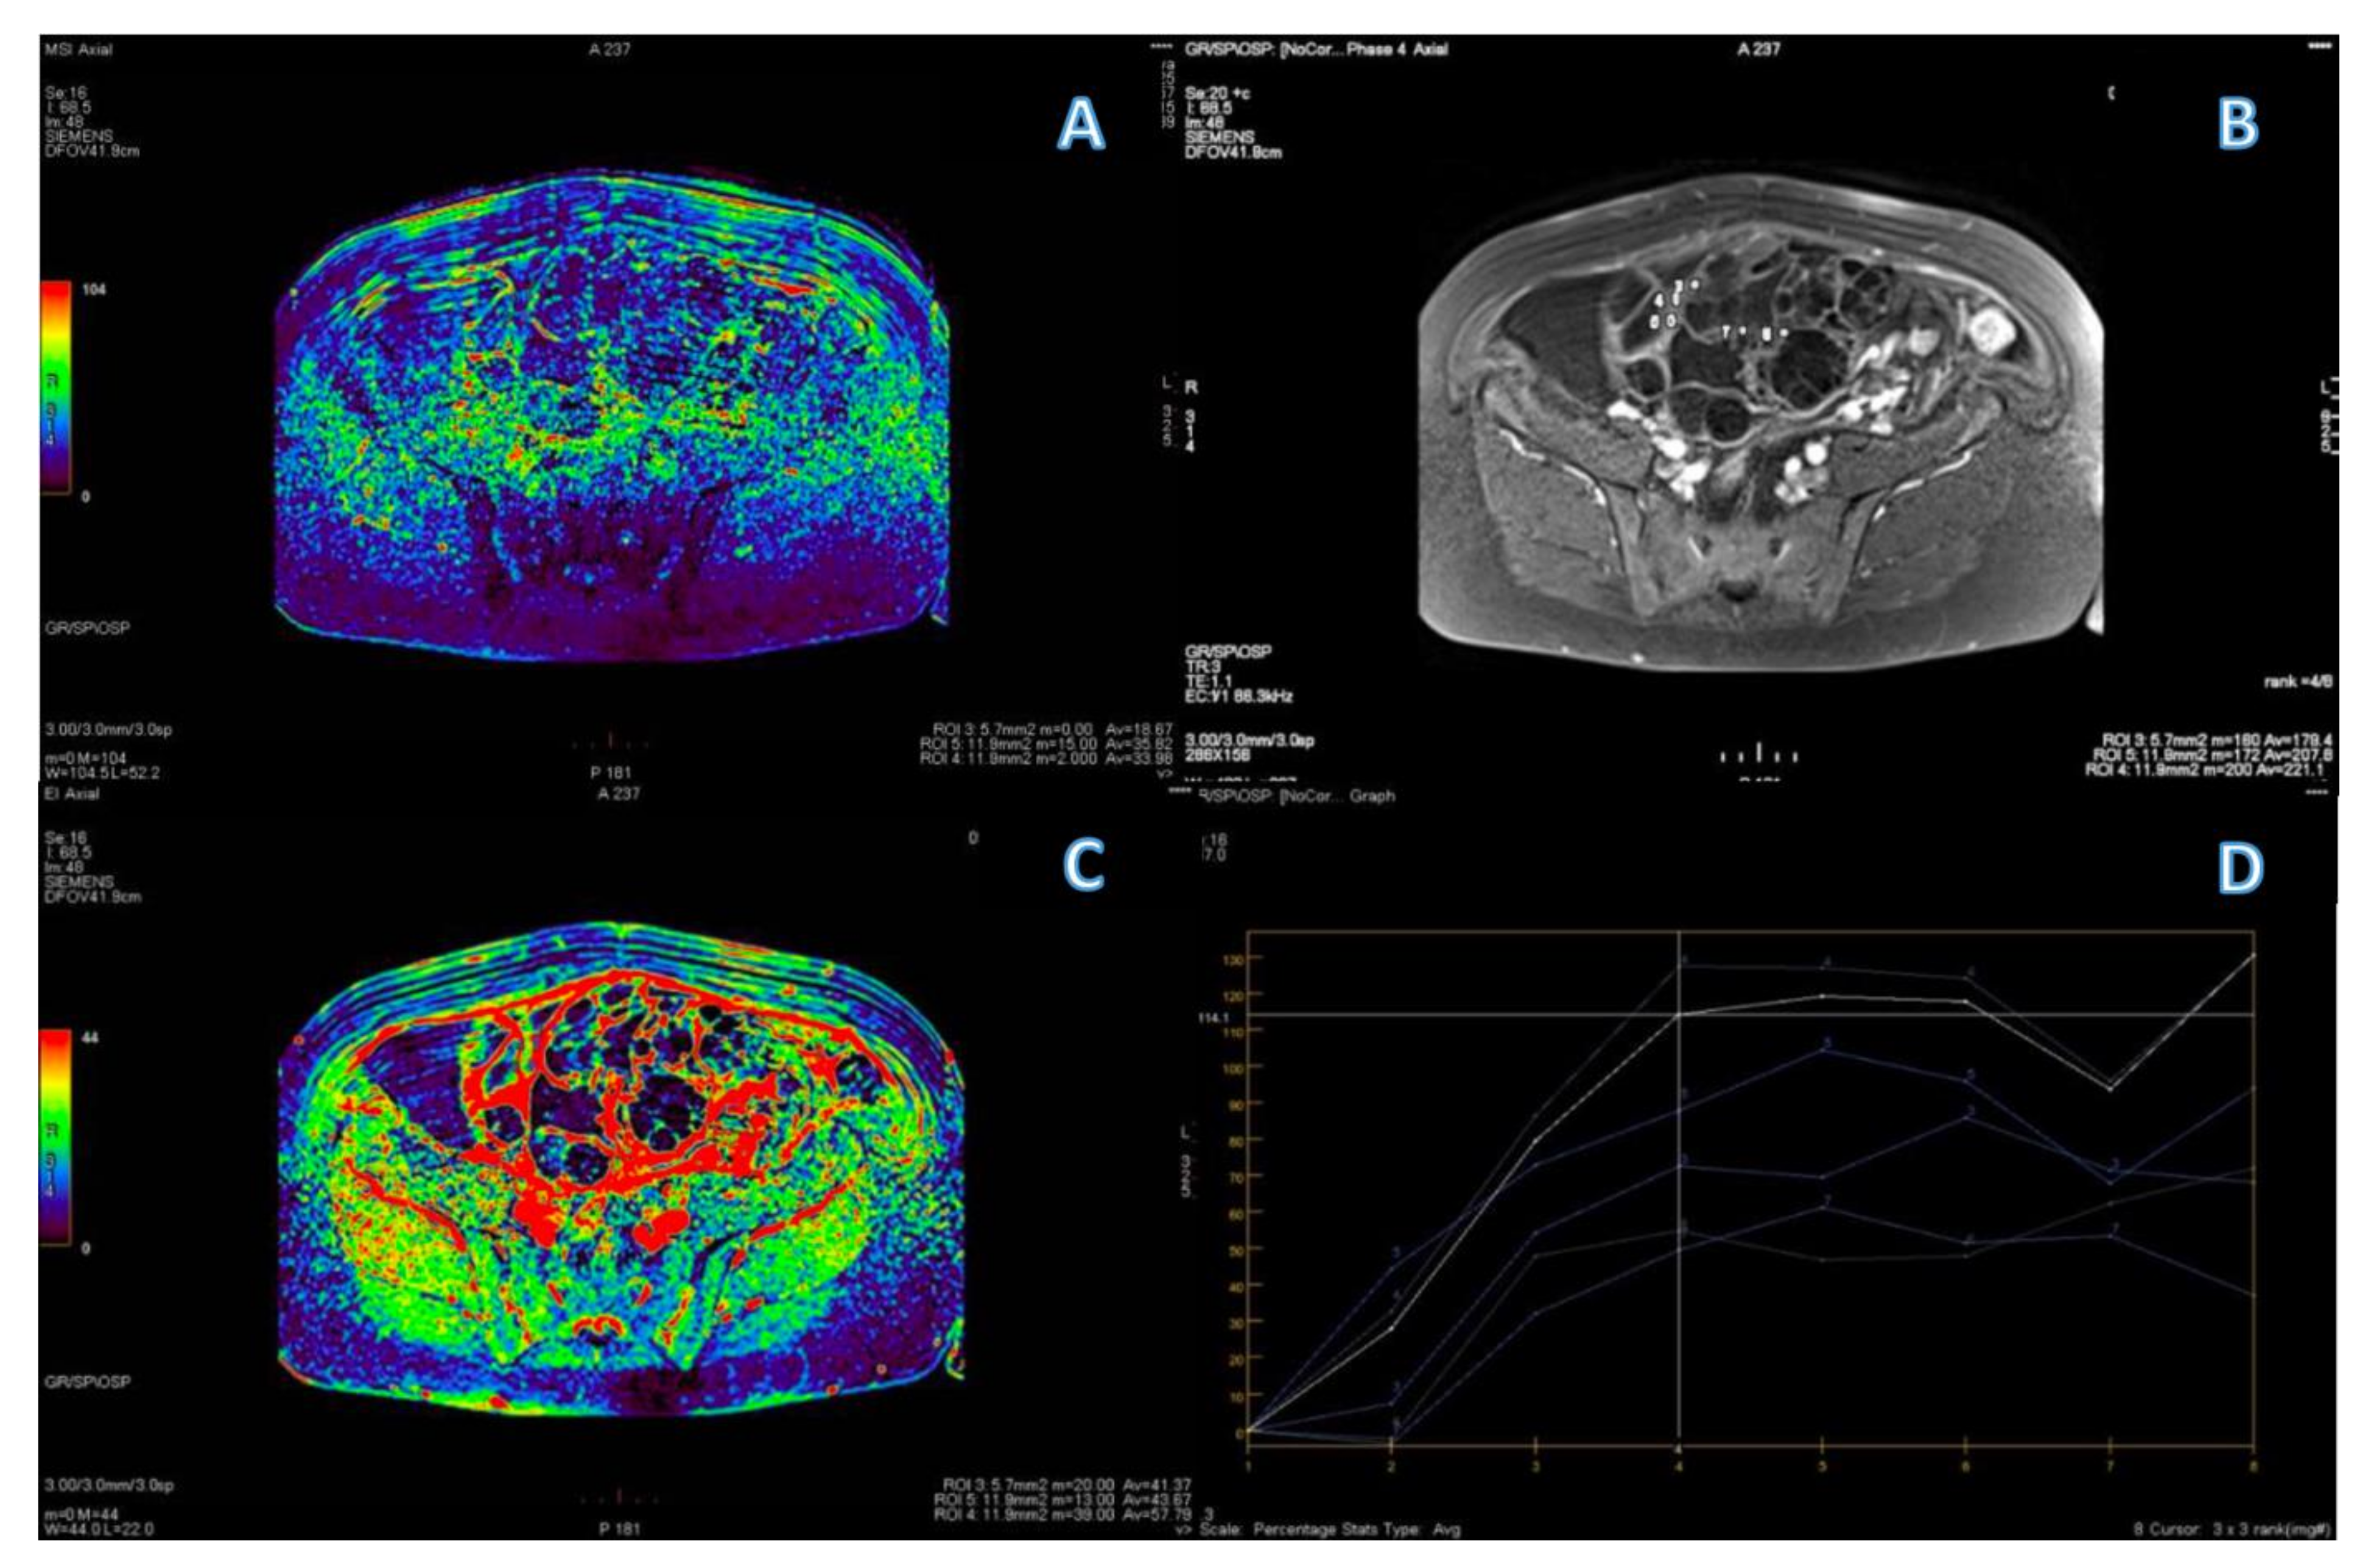

3.4. ROC Curve for LGSC vs. MOC